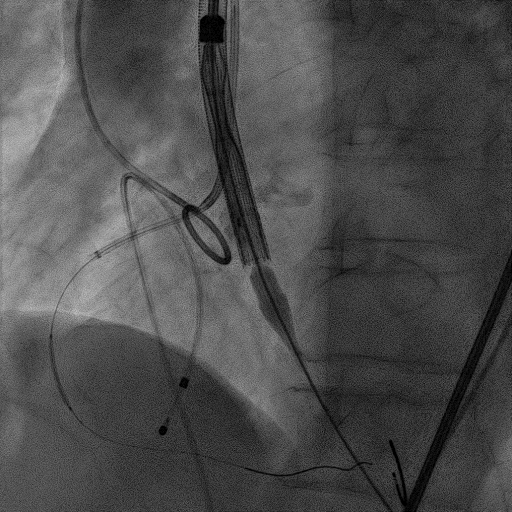

手术过程:

患者麻醉方式采取监护麻醉,建立静脉通路后,穿刺右侧股动脉预置两把Proglide缝合器。穿刺右侧股静脉,置入6F鞘管,将临时起搏器到位。经右股动脉行冠脉造影提示冠脉无有意义狭窄。加硬导丝送至左心室内,22mm球囊预扩张,Venus-A L26瓣膜精准定位并释放,后使用22mm球囊后扩张,瓣膜形态良好,结果满意。应用ProGlide缝合右股动脉穿刺部位并拔除临时起搏电极。术后患者即刻苏醒,安全返回普通病房。

主动脉根部造影

22mm球囊预扩张

Venus-A L26瓣膜精准定位

22mm球囊后扩张

瓣膜形态良好,结果满意